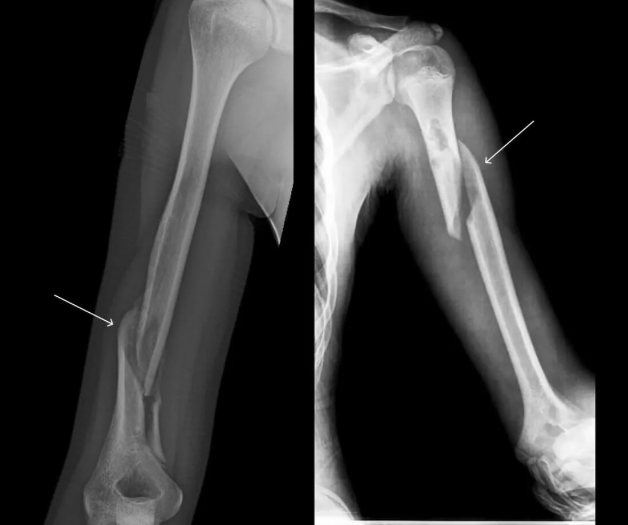

Çigın zeperleri

32

1